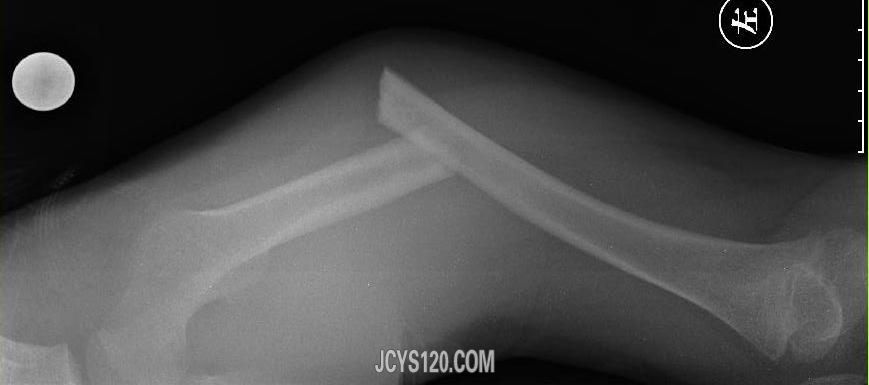

• 颅脑外伤 attach_img

• wjl8742693 2013-7-21

• 患者,女性,52岁,颅脑外伤半小时, 今晨两人骑电瓶车互撞,致其头部倒地,短暂意识丧失,稍感头痛,呕心,未吐,全身多处软组织损伤。 体检神清,痛苦貌,意识清楚,查体合作,头颅左侧上眼眶和颞部见8×6cm一个 ...  阅读全文>